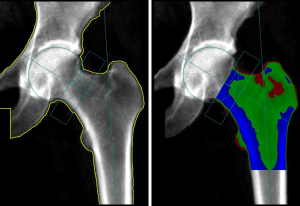

The role of DXA is central in the study of body composition (BC) thanks to its ability to differentiate FM, non-bone lean mass (LM) and BMC at both the regional and the whole-body level (Figure 2) (49-60). DXA relies on the use of two X-ray beams of different energy; the measurement of the “R value” is calculated as the ratio between the degree of attenuation of the lower energy and the higher energy beam. The R value is specific for each tissue and depends on the patient’s soft tissue composition. From the R value, using complex algorithms, it is possible to derive the amount of BMC in pixels containing bone. BMD is then calculated as the ratio BMC/area (in g/cm2). In pixels without bone, soft tissue is further characterized as FM and non-bone LM (61,62).

Other non-BMD parameters can be derived from 2D DXA images in addition to TBS. Hip Structural Analysis (HSA; Hologic, Bedford, MA, USA) and Advanced Hip Assessment (AHA; GE-Lunar, Madison, WI, USA) are two recently developed software products that can be applied to a standard DXA scan to automatically derive various parameters related to bone geometry and bone strength, including hip axis length (HAL), cross sectional area (CSA), outer diameter (OD), section modulus (SM), buckling ratio (BR), cross-sectional moment of inertia (CSMI) and neck shaft angle (NSA) (86,87). According to the ISCD 2015 official positions, among hip geometry parameters derived from DXA, only the HAL is associated with hip fracture risk in postmenopausal women (88). HAL, by definition, is the distance (in mm) from the lower base of the greater trochanter, through the femur neck, to the inner pelvic brim (Figure 4). At the beginning of the 90s, Faulkner et al. demonstrated the existence of an association in postmenopausal women between a longer HAL and increased risk of femoral neck fractures (OR =1.9) and trochanteric fractures (OR =1.6) even after adjustment for age, femoral neck density, height, and weight. No significant association between the neck width or the NSA and risk of hip fracture was documented (89). Recently, Leslie et al. confirmed the role of HAL as a BMD and FRAX-independent risk factor for hip fracture in women and, additionally, reported the same independent effect of longer HAL on hip fracture risk in men (90,91). This data was however derived from a single clinical registry. These preliminary results, albeit promising, need further validation with large scale studies and at the current state of investigations, there is not sufficient evidence to support this statement in men.